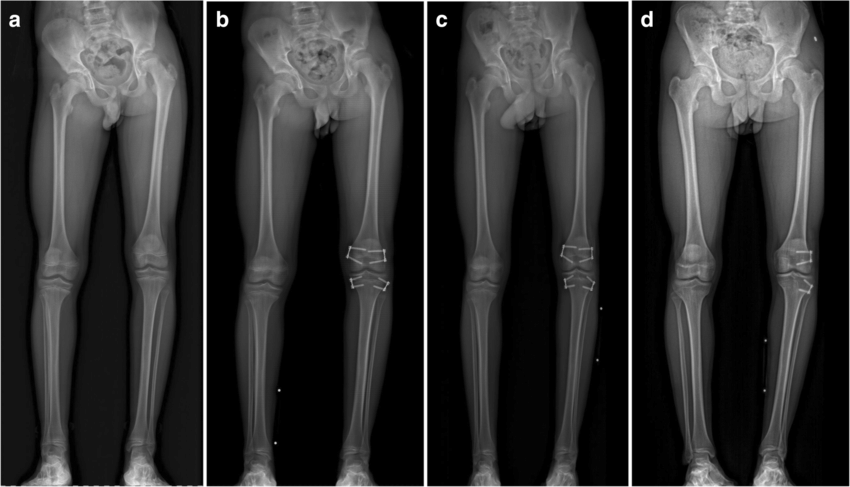

Treatment options for LLD depend on the severity of the discrepancy, the child's age, and the underlying cause. They include: